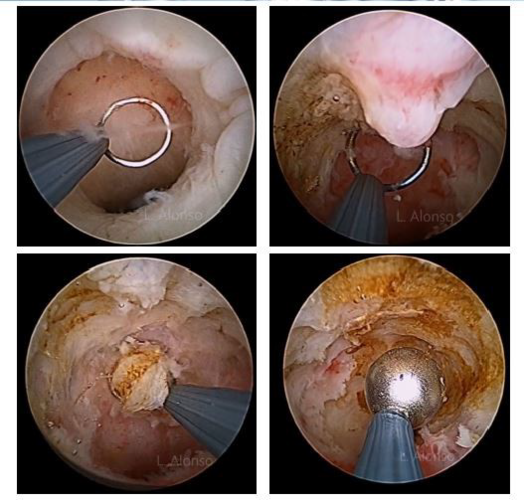

【镜·界】宫腔镜和腹腔镜下的剖宫产瘢痕憩室修复术

子宫憩室宫腔镜图片

子宫切口憩室的图片